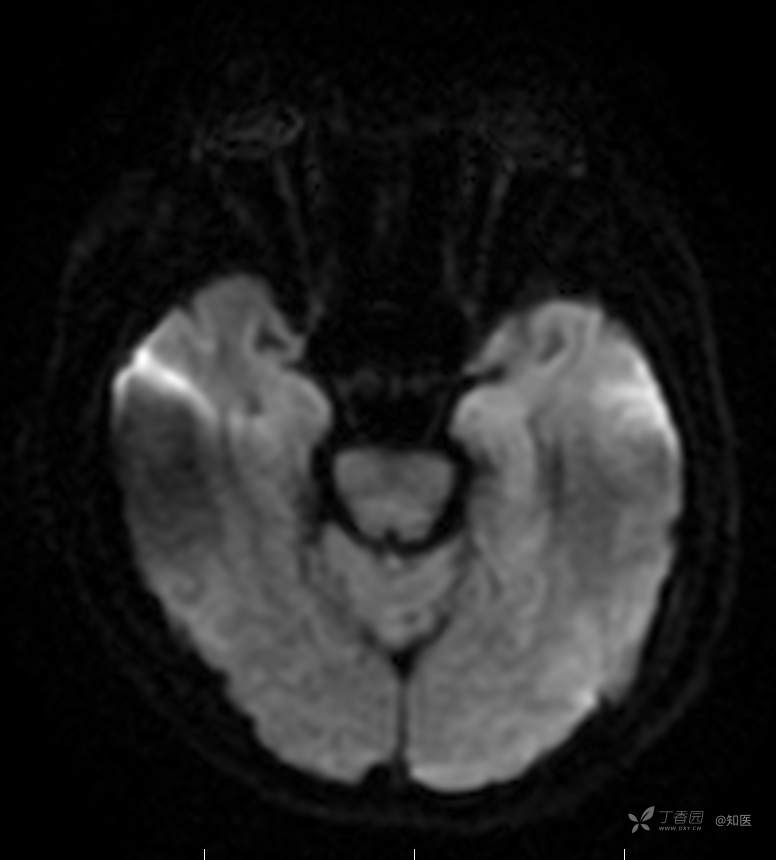

2021-6-15 ADC

2021-06-16日晨查房,患者自觉入院治疗后肢体无力症状较前稍改善,仍有活动后气短,余未诉特殊不适。ALSFRS-R评分:44分(单项均大于等于2分)。血压:123/63mmHg。神经系统查体:GCS 15分,右利手,查体合作,问答切题,粗测智能基本正常。额纹对称,双眼闭目紧,双侧瞳孔等大等圆,直径约3.0mm,对光反射灵敏,眼球运动自如,无眼震,双侧鼻唇沟对称等深,口角无歪斜。悬雍垂居中,双侧软腭抬举良好,咽反射灵敏、转颈、耸肩均一致有力。颈屈肌、颈伸肌力量5级。伸舌居中,无舌肌纤颤及萎缩。双侧岗上肌、岗下肌可见萎缩;双侧三角肌可见偶发肉跳、肌力5级,左侧肱二头肌肌力4+级、右侧4-级,双侧肱三头肌肌力4+级;双手握力可,双手大小鱼际肌及第一骨间肌可见萎缩,左侧明显,左侧手腕背伸力量4级、右侧4+级,双侧拇短展肌肌力4-级,双侧示指伸肌肌力3级,左侧指总伸肌肌力4级、右侧4-级,双侧小指展肌肌力4-级。双上肢肌张力对称减低。左侧肱二头肌反射迟钝、右侧未引出,双侧桡骨膜反射及肱三头肌反射未引出。左侧胸大肌反射阳性、右侧未引出,双侧Rossolimo征阳性、Hoffmann征阴性,下颌反射阴性。腹壁反射未引出。双下肢可见肌肉萎缩,以左侧明显;左侧髂腰肌肌力4级、右侧4-级,双侧股四头肌肌力5级,双足背伸力量3级,左足跖屈力量4级、右足4+级。双下肢肌张力对称基本正常。双侧膝腱反射、跟腱反射迟钝,双侧跖反射消失,双侧巴氏征未引出。右侧大腿外侧肌肉活检瘢痕周围浅感觉缺失,余肢体及躯干深浅感觉正常,共济运动对称正常。颈软,无抵抗,双侧布氏征及克氏征均阴性。辅助检查:微量元素(钙、镁、铁、铜、锌),微量元素测定(铅,镉)[复][2021-6-16 16:11:07]:钙1.19mmol/l;铁9.00mmol/L。急诊电解质七项[复][2021-6-16 10:41:41]:钾3.55mmol/L。血细胞分析+五分类[2021-6-16 9:57:17]:淋巴细胞百分比19.5%。[头颅,扩散成像(DWI)][头颅,磁敏感成像(SWI)][头颅,水抑制成像(FLAIR)][2021-6-16 18:10:50]:1.多发腔梗,脑白质脱髓鞘,脑萎缩。2.DWI:脑实质内未见明显高信号。3.磁敏感成像脑实质内未见明显异常信号灶。MMSE:26分(高中文化水平)。MoCA:23分。ADL评分:14分。ECAS评分:96分(ALS特异67分、ALS非特异29分)。肌电图:提示颈髓、腰髓、胸髓和延髓支配肌肉可见活动期神经源性损害,颈髓和腰髓支配肌肉同时可见慢性期神经源性损害;提示脊髓前角细胞损害可能,请结合临床。心电图大致正常。外送基因检查:TBK1基因杂合子,提示额颞叶痴呆和(或)肌萎缩性侧索硬化症4型。二线主治医师查看患者后示:1.患者基因检查结果显示TBK1基因杂合子,提示额颞叶痴呆和(或)肌萎缩侧索硬化症4型,结合外院影像学检查可见额颞叶萎缩明显,来院后复查头颅FLAIR+DWI+SWI亦提示脑萎缩,量表评估提示认知功能稍减退,ECAS评分基本正常。综上,修正诊断:肌萎缩侧索硬化症(ALS) 额颞叶变性 低钾血症 高血压2级(高危) 多发腔隙性脑梗死。因TBK1基因引起的额颞叶痴呆和(或)肌萎缩侧索硬化症为常染色体显性遗传,患者父亲已逝,母亲健在,诉无明显认知功能障碍或肌肉萎缩等表现,建议患者母亲抽血送检,进一步明确致病基因来源,必要时患者子女也可行基因检查进一步明确。2.患者目前诊断基本明确,根据文献报道,合并FTD的ALS患者整体生存周期较短(约19个月),目前患者发病已1年余,应充分与患者家属沟通病情,告知疾病预后及生存周期情况,同时建议开始口服利鲁唑片,延缓疾病进展。余治疗方案暂不予调整。密观病情变化,遵嘱执行。

2021-06-18出院总结: 卫某某,男,60岁,以“四肢僵硬1年,加重伴无力半年”之主诉入院。查体:生命体征平稳,心肺腹查体无明显异常。神经系统查体:GCS 15分,右利手,查体合作,问答切题,粗测智能基本正常。额纹对称,双眼闭目紧,双侧瞳孔等大等圆,直径约3.0mm,对光反射灵敏,眼球运动自如,无眼震,双侧鼻唇沟对称等深,口角无歪斜。悬雍垂居中,双侧软腭抬举良好,咽反射灵敏、转颈、耸肩均一致有力。颈屈肌、颈伸肌力量5级。伸舌居中,无舌肌纤颤及萎缩。左侧肱二头肌肌力4+级、右侧肱二头肌及双侧三角肌肱三头肌肌力5级;左手大小鱼际肌可见萎缩,左手握2指松、右手握力可,左手拇短展肌、示指伸肌、指总伸肌及抬腕力量3级,右手拇短展肌、示指伸肌、指总伸肌及抬腕力量4-级。双上肢肱二头肌反射、肱三头肌反射、桡骨膜反射均对称减低;双侧Hoffmann征、Rossolimo征、胸大肌反射及掌颏反射阴性,下颌反射阴性。双侧上、中、下腹壁反射可引出。左侧髂腰肌肌力4-级、右侧髂腰肌肌力4级,双侧股四头肌肌力5-级;右足背伸力量3级、左足背伸力量2级,双足跖屈力量5级。双下肢膝腱反射、跟腱反射对称减低;双侧膝阵挛、踝阵挛未引出。双侧巴氏征、Chaddock征均未引出。右侧大腿外侧肌肉活检处周围浅感觉减退,余四肢及躯干部深浅感觉正常,共济运动对称正常。颈软,无抵抗,双侧布氏征及克氏征均阴性。辅助检查:肌电图(2021-05-08,某军医大学附属医院):神经源性损害(颈段、腰骶段受累,胸段可疑;重复神经电刺激(低频、高频)可见左腋神经递减现象。 肌肉活检(2021-05-18,某军医大学附属医院):(右股四头肌)考虑神经源性损害,建议结合临床除外运动神经元病等。入院诊断:1.肢体无力:肌萎缩侧索硬化症(ALS);2.高血压1级(中危)。入院后查血清蛋白电泳:α2-球蛋白6.50%。凝血六项:血浆凝血酶原时间比值0.93;凝血酶原国际标准化比值0.93。贫血因子三项:维生素B12>1476.00pmol/L。平诊肝功十三项+平诊心肌酶谱五项+血同型半胱氨酸测定+平诊血脂八项+平诊肾功七项+平诊电解质八项:尿素3.05mmol/L;肌酐49umol/L;钾3.15mmol/L;高密度脂蛋白0.99mmol/L;载脂蛋白A1.131g/L;脂蛋白(a)333mg/L;肌酸激酶420U/L;总胆红素22.1umol/L;直接胆红素5.4umol/L。微量元素(钙、镁、铁、铜、锌),微量元素测定(铅,镉):钙1.19mmol/l;铁9.00mmol/L。急诊电解质七项:钾3.55mmol/L。血细胞分析+五分类:淋巴细胞百分比19.5%。[头颅,扩散成像(DWI)][头颅,磁敏感成像(SWI)][头颅,水抑制成像(FLAIR)]:1.多发腔梗,脑白质脱髓鞘,脑萎缩。2.DWI:脑实质内未见明显高信号。3.磁敏感成像脑实质内未见明显异常信号灶。MMSE:26分(高中文化水平)。MoCA:23分。ADL评分:14分。肌电图:提示颈髓、腰髓、胸髓和延髓支配肌肉可见活动期神经源性损害,颈髓和腰髓支配肌肉同时可见慢性期神经源性损害;提示脊髓前角细胞损害可能。血尿粪常规、免疫八项、风湿三项、血沉、传染指标、血同型半胱氨酸、糖化血红蛋白等未见明显异常。心电图、肺通气功能大致正常。住院期间给予营养神经、清除氧自由基等对症支持治疗。现患者诊断基本明确,生命体征平稳,一般情况良好,可予今日出院。出院诊断:1.肌萎缩侧索硬化症(ALS);2.额颞叶变性;3.低钾血症;4.高血压2级(高危);5.多发腔隙性脑梗死。出院医嘱:1.注意休息,加强营养,低盐、高蛋白高纤维素饮食,注意休息,适当锻炼,避免剧烈运动及重体力劳动。2.出院继续口服药物:甲钴胺 500ug/次,3次/日;辅酶Q10 10mg/次,3次/日;维生素E 100mg/次,2次/日;美金刚 10mg/次,1次/日;利鲁唑片,50mg/次,2次/日,与餐间隔1.5-2小时。3.出院继续用依达拉奉(必存)60mg+0.9%氯化钠 200ml,静滴,1次/日(首疗程14天,后每疗程10天,间隔20天,共使用6个疗程)。4.1月后门诊复查血常规、肝肾功能、电解质功能;3月后我科门诊再次复诊。5.不适随诊。